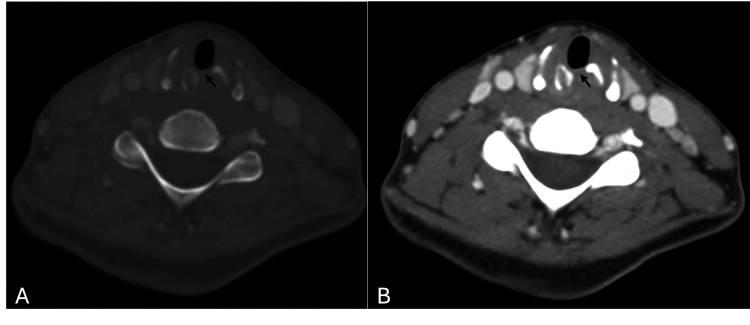

患者一个月后复查提示症状进一步改善,纤维喉镜检查显示声带外展仅轻度受限。出院两个月后的随访中,完全无症状,声带活动正常,CT扫描声门下积液完全消失(图2)。

图2 (A,B)计算机断层扫描图像显示声门下脓肿消失,左侧环状软骨已知移位骨折(箭头)